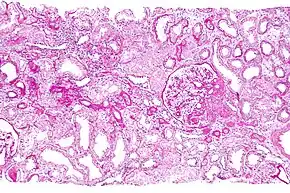

- A kidney ultrasound in this condition usually shows normal or small sized kidneys (occasionally cysts are present). However, since cysts are present in many normal individuals, these cysts are not helpful in making a diagnosis, therefore a kidney biopsy can be done to determine if the individual has this disease. Kidney biopsy is a procedure where a needle is inserted into the kidney and removes a small piece of kidney tissue. This tissue is then examined under a microscope.[18][19]